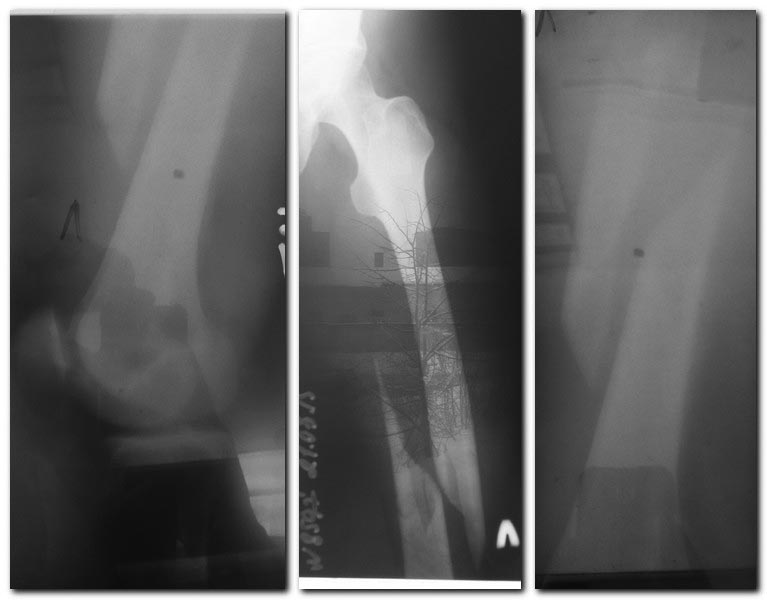

Пациентка, 57, лет, без отягощенной соматической патологии.Травма на

прошедших выходных.

Перелом диафиза бедра косой, с раскалыванием по длине дистального

отломка. На вытяжении.

Склоняюсь к открытой репозии пластиной LSP, т.к. думаю есть интерпозиция

м.тканей и опасность расколоть дистальный фрагмент при заведении гвоздя.

Есть мнение з.о. сделать ретроградный гвоздь с открытой репозицией и

серкляжем. Не думаю, что это менее травматично.